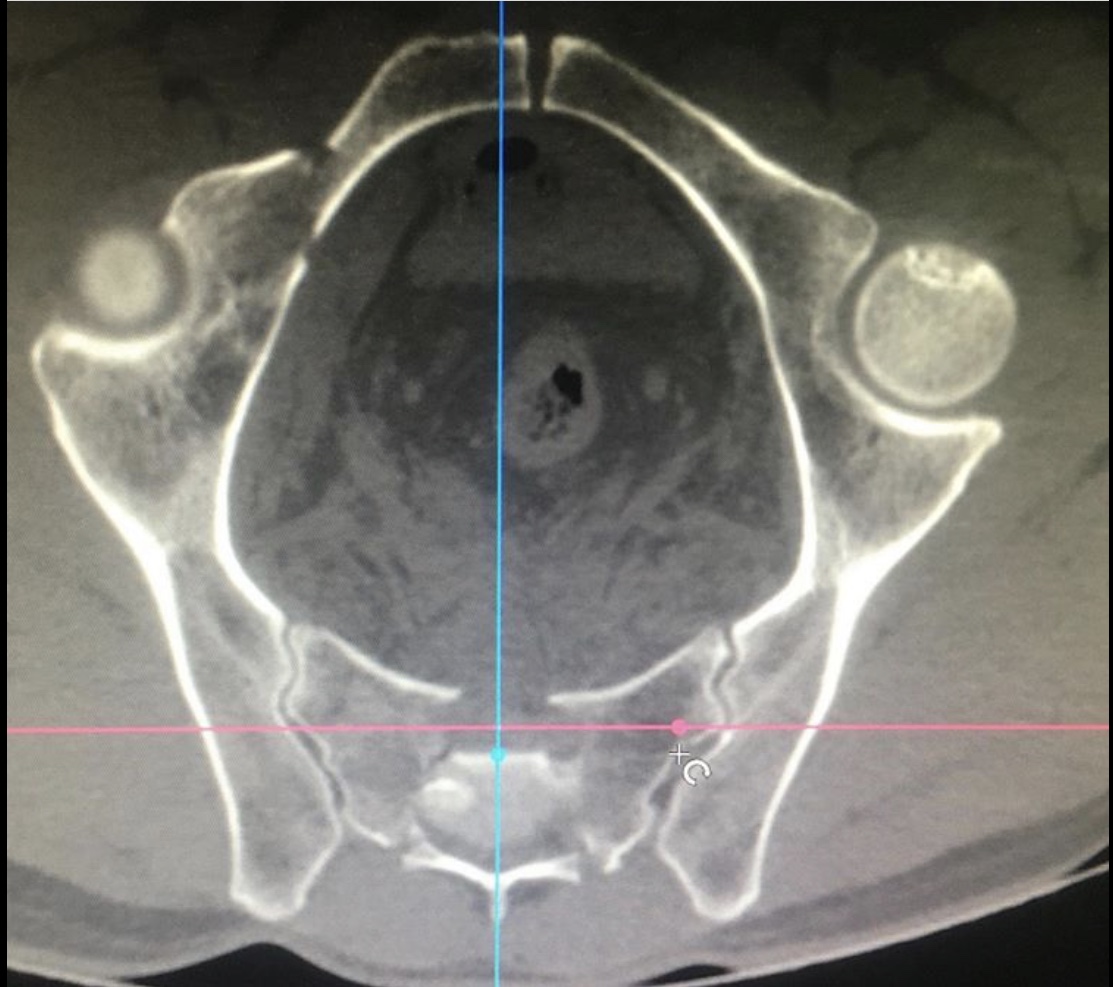

Диагноз неутешительный: двусторонний нестабильный перелом крестца, осложнённый каудопатией и нарушением функции тазовых органов, перелом типа RoyCamille 2 с компрессией корешков конского хвоста.

Как рассказал хирург – травматолог – ортопед нашей клиники Руслан Ильгизарович Закиров, при поступлении пациенту была выполнена стабилизация костей таза в аппарате внешней фиксации. После стабилизации гемодинамических показателей выполнена двусторонняя пояснично-тазовая фиксация, сакротомия на вершине деформации, остеосинтез реконструктивными пластинами.